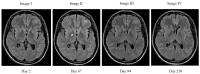

We describe the successful use of isavuconazole for treatment of an HIV-positive patient with cryptococcal meningitis following induction therapy with liposomal amphotericin B and flucytosine. Because the Cryptococcus neoformans isolate from cerebrospinal fluid had a borderline minimum inhibitory concentration of 8 mg/L, initial consolidation therapy was given with a daily dose of fluconazole 1200 mg based on area under the curve to minimum inhibitory concentration modelling data. Toxicity, and the radiological emergence of a cryptococcoma in the setting of immune reconstitution inflammatory syndrome, prompted a therapeutic switch to isavuconazole. Subsequent imaging after 19 weeks of isavuconazole shows a significant reduction in cryptococcoma size from 11 mm to complete resolution. The patient remains well after 210 days of therapy with a view to completion of treatment after 1 year.